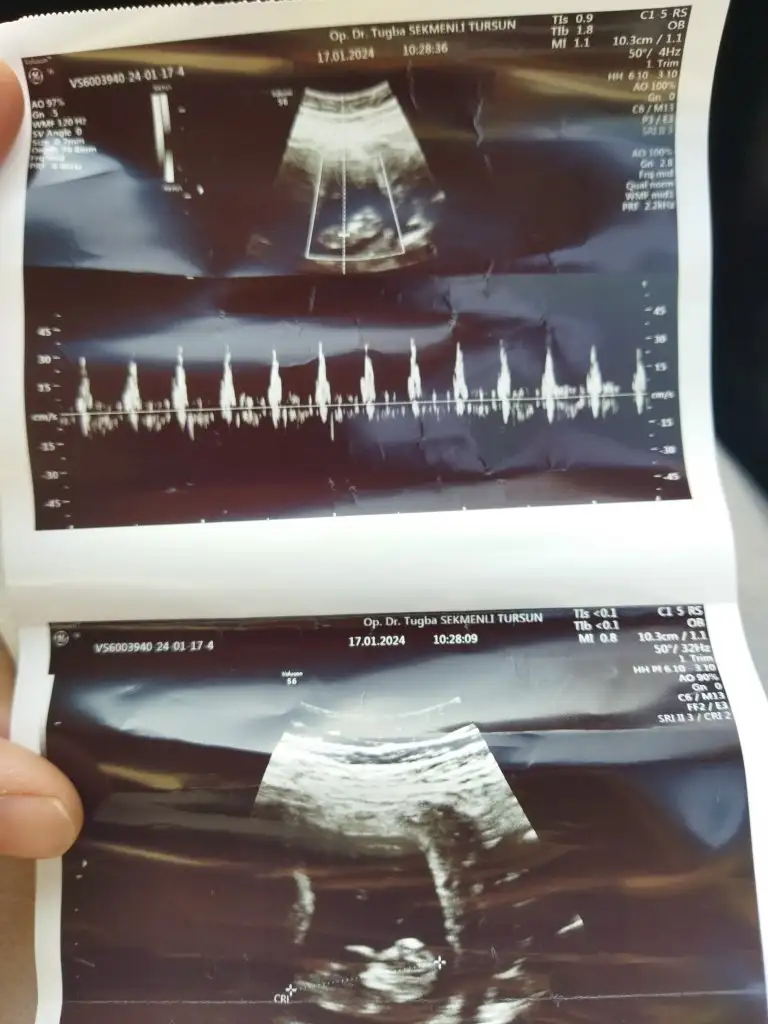

Sizce nedir cinsiyet kızlar 🥰 11+2

Kızlar herkese selam ! 8 haftalık gebeyim ve hemen hemen her anne adayı gibi cinsiyetini aşırı merak ediyorum. Tabikide önceliğim sağlıklı olması bunu söylemeye bile gerek yok, bizimki biraz olayım heyecanı :) Ramzi teorisi diye bir şey gördüm konudan anlayan ekteki ultrasonda fotoğrafıma göre cinsiyetiyle ilgili tahminde bulunabilir mi acaba?

Cinsiyeti nedir acaba 😍